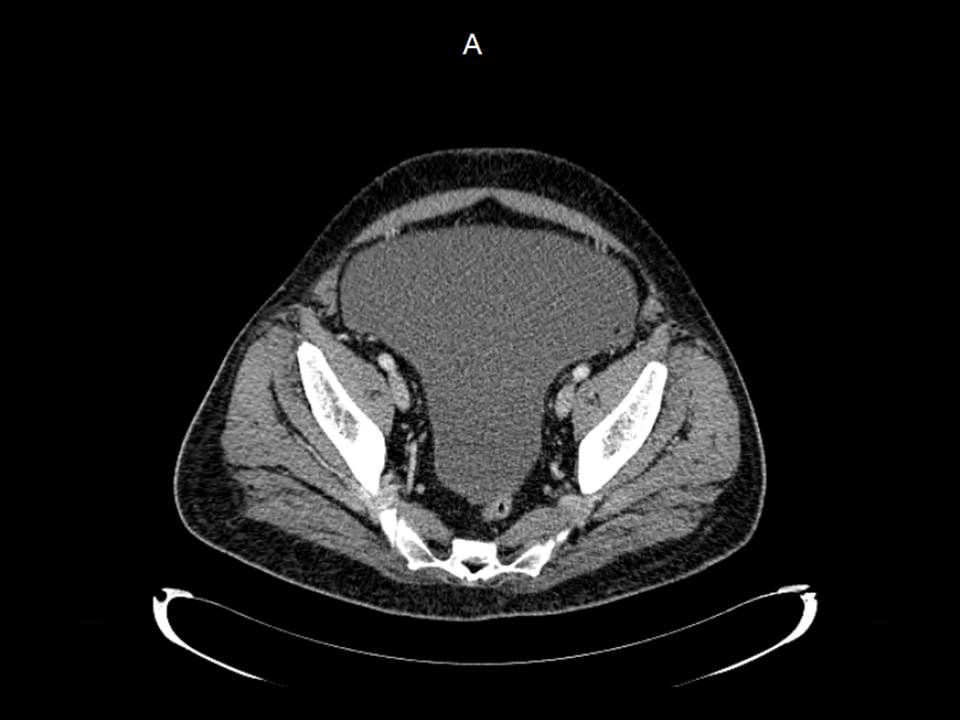

Paciente de 72 años con antecedente de tuberculosis genitourinaria hace 40 años.